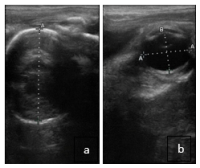

Surgeons Remove Sialolith from Horse’s Cheek

Joe Juice, a 19-year-old American Quarter Horse gelding, was fortunate to be in need of imaging at the same time the Diagnostic Imaging Service was testing new equipment before the opening of the All Species Imaging Center this past summer. A suspected sialolith was confirmed on the right side of his face following a scan in the hospital’s new large bore equine CT. Joe Juice was able to be scanned standing using only mild sedation. Equine Surgeons were then able to remove the sialolith with a standing surgery that also only required sedation instead of full anesthesia.

Equine Reproduction Specialists Urge

Late Gestation Ultrasound Exams

With foaling season right around the corner, specialists in the UC Davis Equine Reproduction Service are urging their clients to schedule ultrasounds late in their mares’ pregnancies. Once a mare is confirmed pregnant early in gestation, she is often rechecked shortly afterward to confirm embryo or fetal viability. “In many cases, no further examinations are performed until foaling,” said Dr. Catherine Renaudin, chief of the Equine Reproduction Service at the William R. Pritchard Veterinary Medical Teaching Hospital (VMTH). “However, additional ultrasound examinations later in pregnancy are strongly recommended to improve pregnancy outcomes and reduce the risk of complications for both mare and foal.” A brief, non-invasive transrectal ultrasound can provide valuable information.